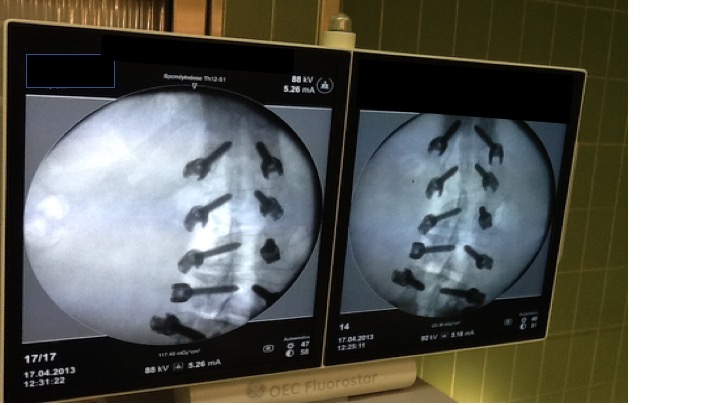

Die Skoliosekorrektur von Jugendlichen ist eine riskante Operation. Nicht nur weil das neurologische Outcome für das ganze zukünftige Leben auf dem Spiel steht, sondern auch weil mit dem meist hohen Transfusionsbedarf ein weiterer bislang nicht einschätzbarer Risikofaktor in Kauf genommen werden muss. In einer retrospektiven Studie hat nun ein griechisches Autorenteam den Einfluss eines 3-Komponenten-Programms bestehend der Steuerung des Volumen- und Transfusionsbedarfs mittels Schlagvolumenanalyse, der Einsatz von Tranexamsäure und maschineller Autotransfusion getestet ...